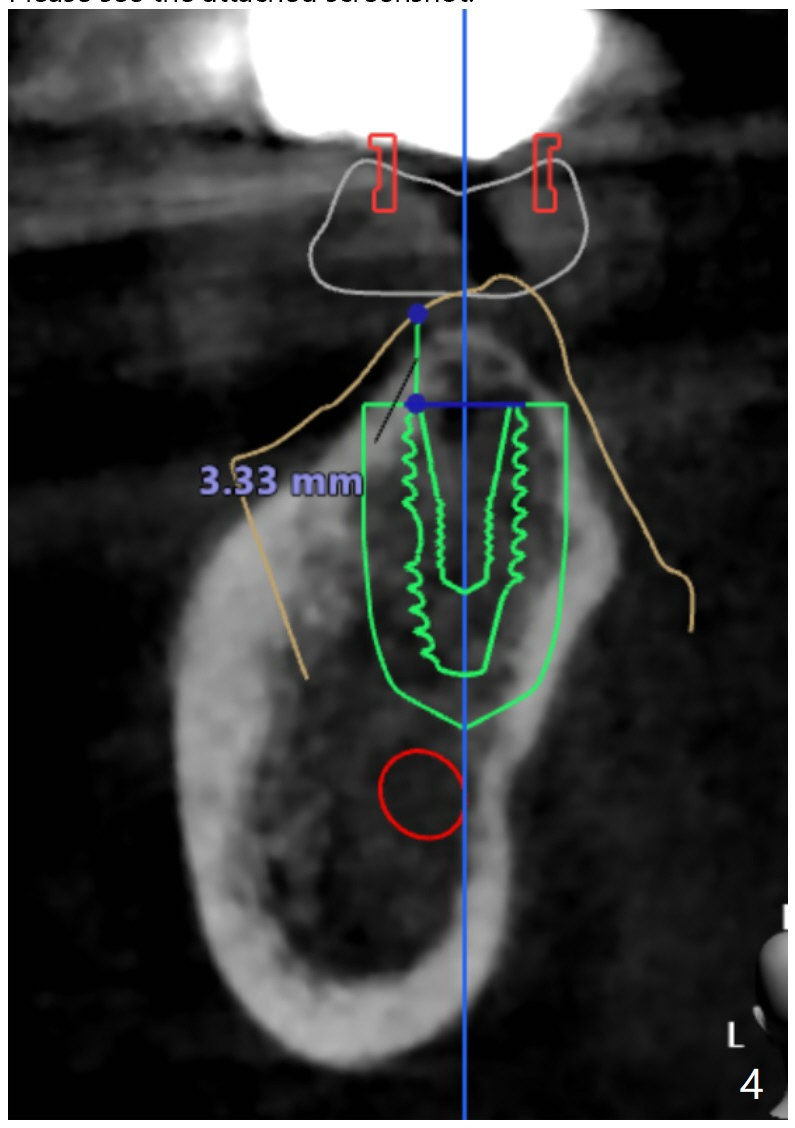

A 57-year-old woman agrees to have implants at #18 and 19 (Fig.1). Since the tooth #15 is supraerupted and there is limited vertical space at #18 (Fig.3), Magicore and FC will be placed at #18 and 19, respectively (Fig.3,2).